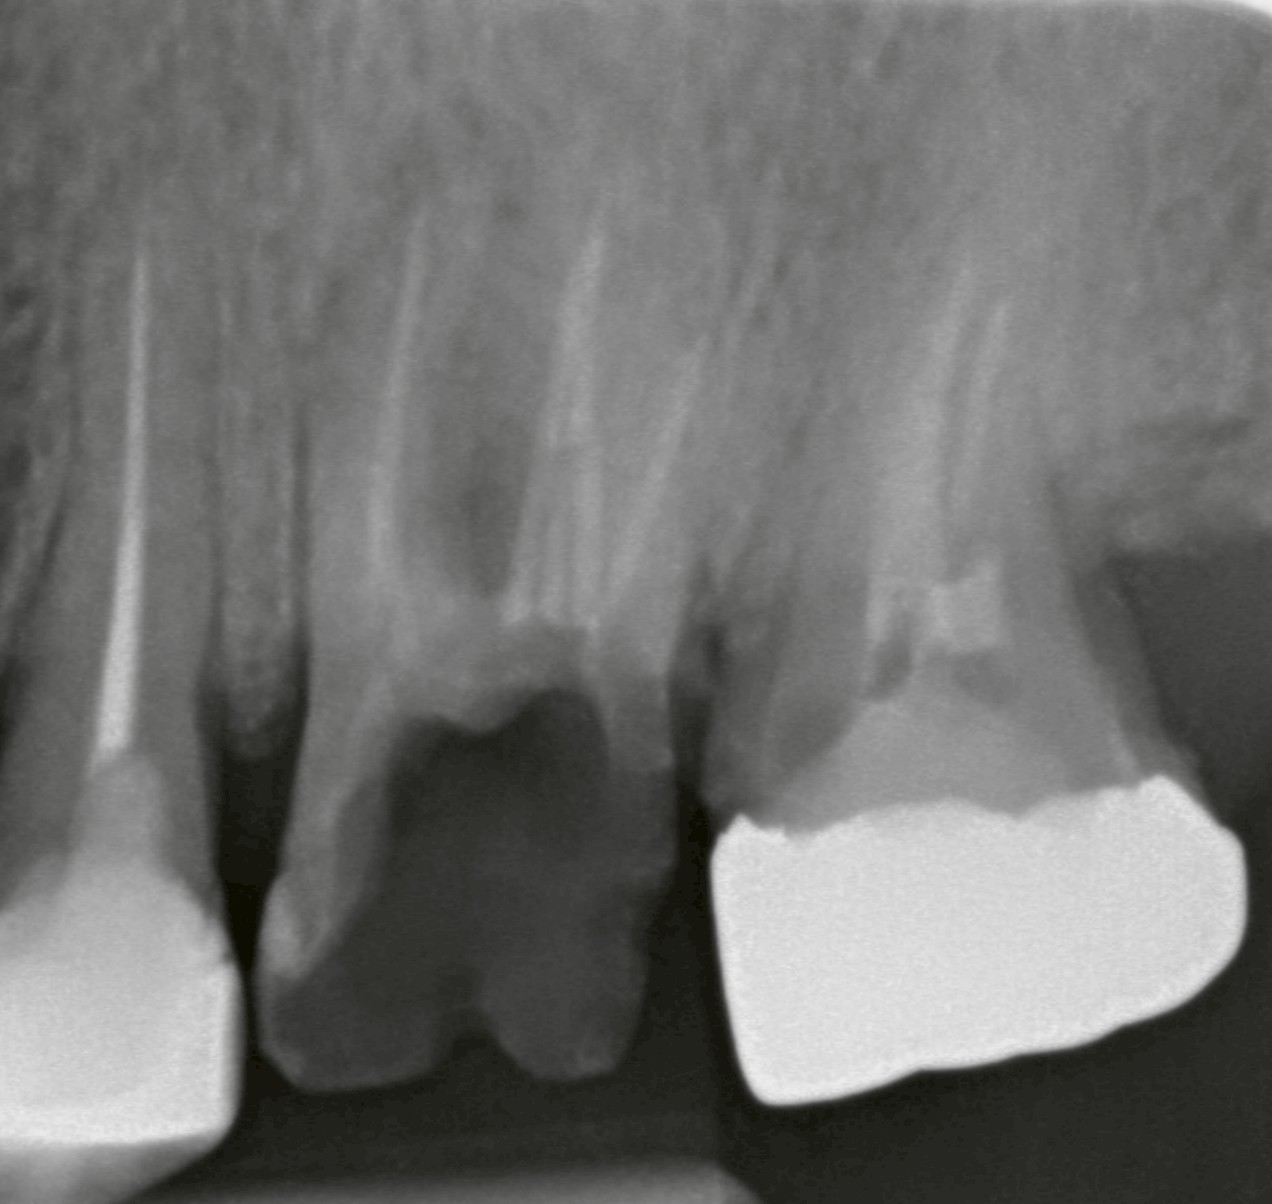

歯根の先に膿が溜まっている、歯周組織に感染が広がっているなど、感染が現在進行形で拡大している場合は、早期抜歯が推奨されます。

・周囲の骨が溶けていく

1. 感染が限局的であること(広範囲でない)

2. インプラントを固定できる十分な骨が残っていること

3. 炎症が強くないこと